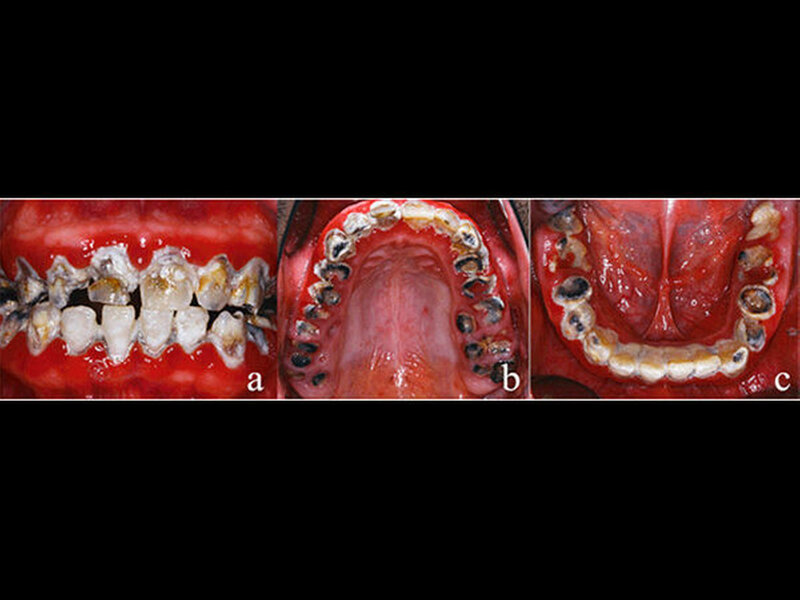

Dem Beginn der zu diesem Zeitpunkt erforderlichen Therapie war eine achtjährige Zahnarztabstinenz und eine damit einhergehende starke Vernachlässigung der Mundhygiene vorausgegangen (Abbildungen 1a-c). Als Grund für die lange Zahnarztabstinenz gab der Patient eine Zahnarztphobie an. Sein äußeres Erscheinungsbild war durchaus gepflegt und stand somit nicht im Einklang mit der oralen Situation. Eine Begründung, warum es zu dem offensichtlich desaströsen Zustand seiner Bezahnung gekommen war, konnte oder wollte der Patient nicht äußern. Die Reaktionen waren auf Nachfrage eher ausweichend und nichtssagend. Der Patient kann als gut situiert bezeichnet werden. Er trat eher introvertiert auf und verbarg seine Zähne beim Reden durch die Lippe.

Der allgemeinzahnmedizinische Befund zeigte ein generalisiert-kariöses Gebiss mit vollständig zerstörten Zähnen im Seitenzahnbereich (Abbildungen 1a-c). Die Zähne 13, 21, 22, 33–43 reagierten beim CO2-Sensibilitätstest positiv. Die restlichen Zähne im Ober- und Unterkiefer zeigten bei Vitalitätsprüfung keine Reaktion. Die Sondierungstiefen lagen im Frontzahngebiet von Ober- und Unterkiefer bei 3–4 mm sowie im Seitenzahnbereich bei größer/gleich 5 mm. Die Ober- und Unterkieferfrontzähne wiesen – im Gegensatz zum Seitenzahnbereich – keine erhöhten Lockerungsgrade auf.